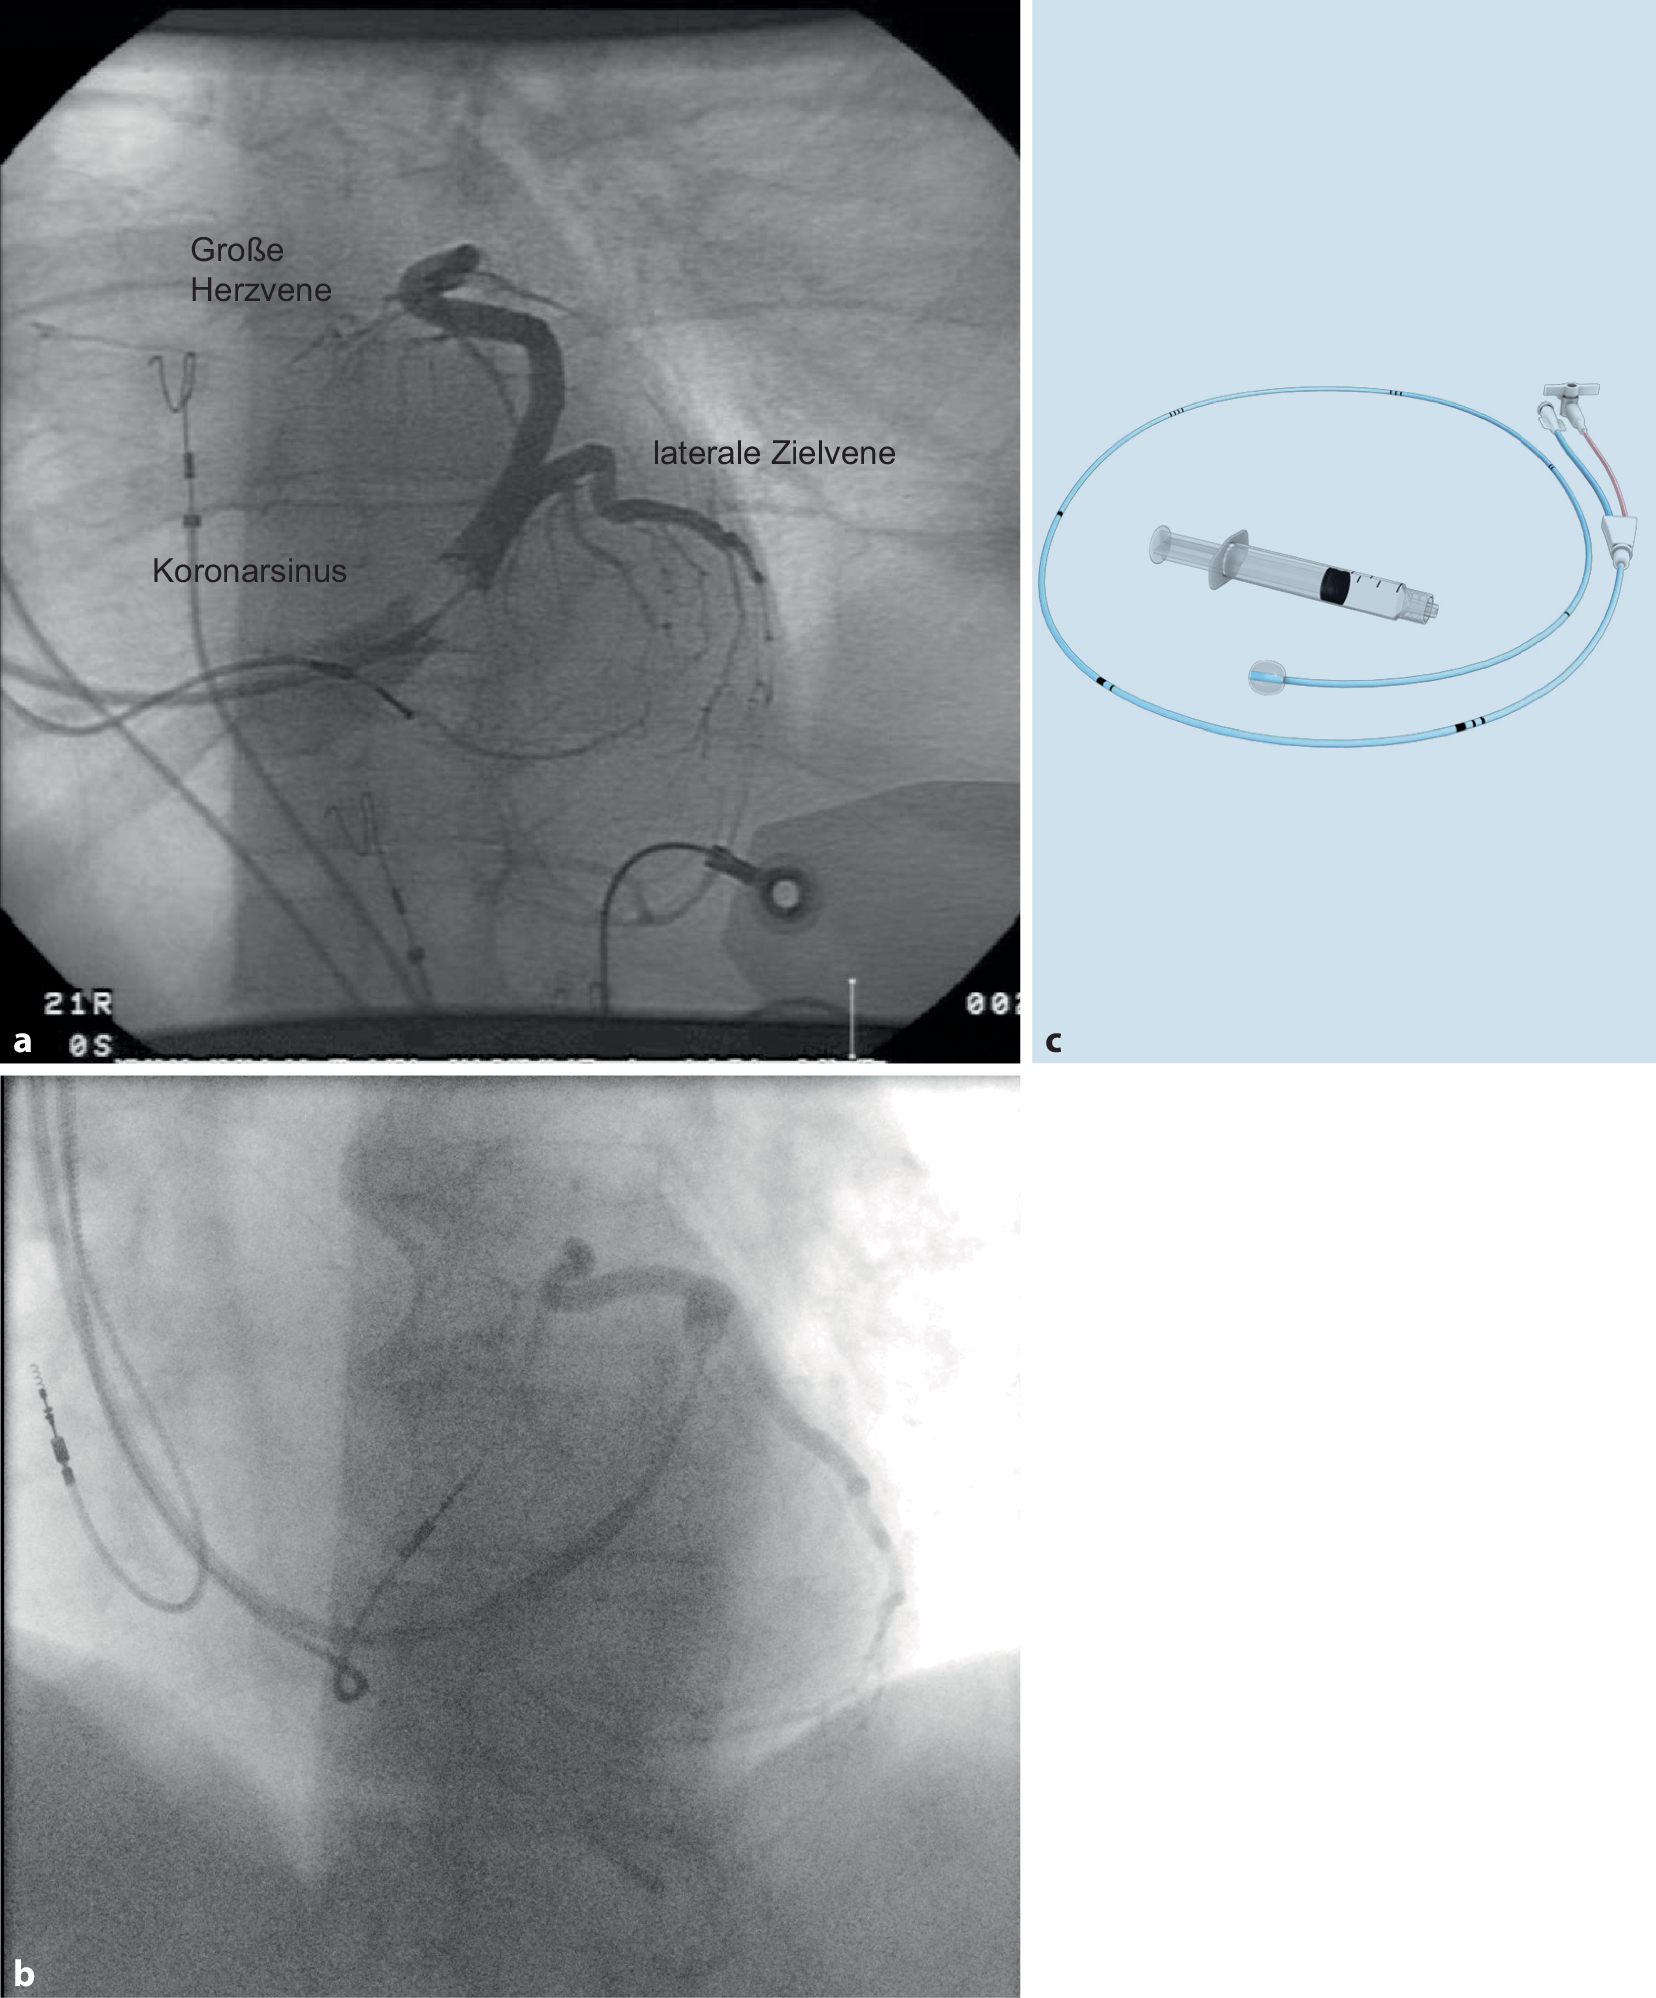

Abb. 6

Ballonvenographie zeigt die Anatomie des Koronarsinus und eine geeignete laterale Zielvene. ab radiologische Aufnahmen; c Ballon-Okklusionskatheter (Abbott)